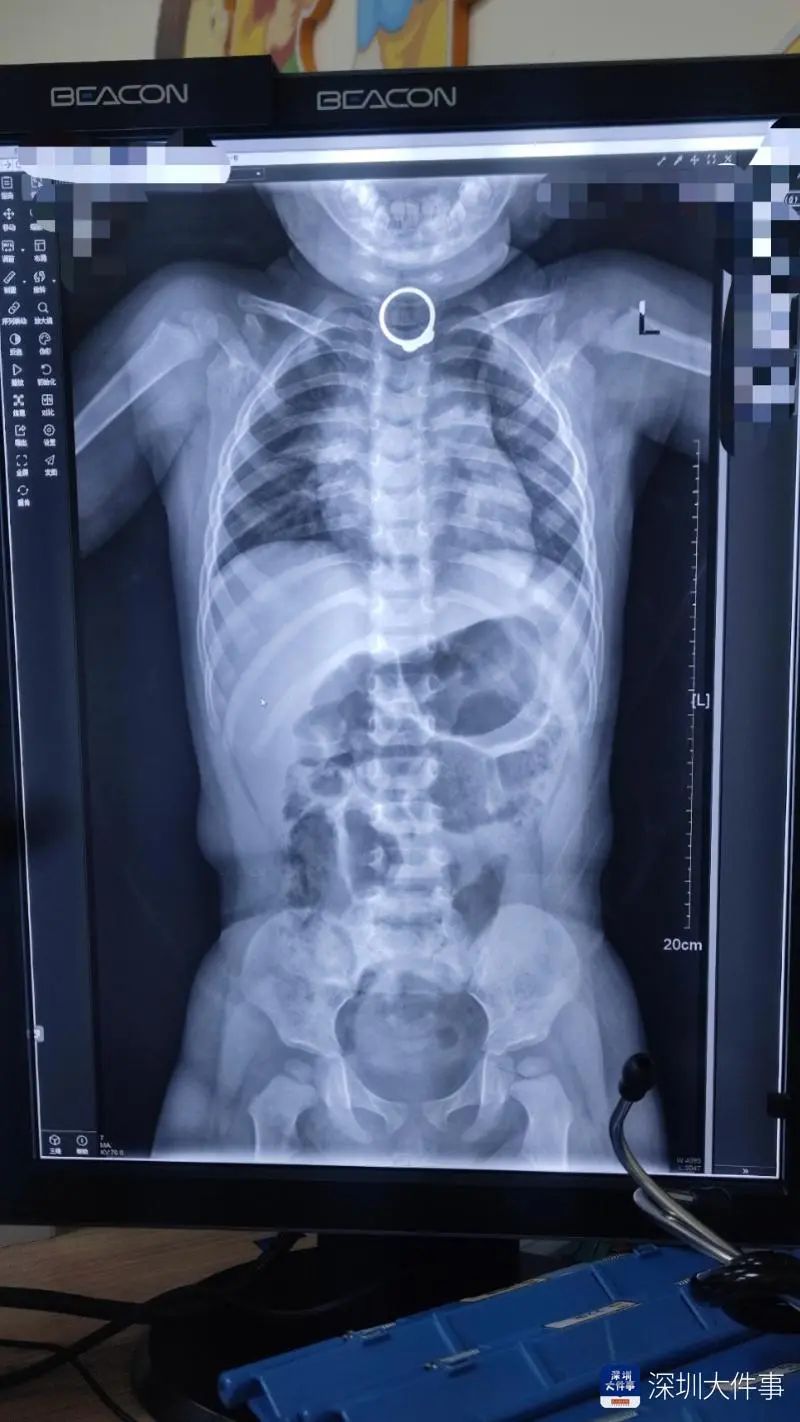

醫(yī)生聽(tīng)了家屬的描述,仔細(xì)給孩子做了體檢,并建議家長(zhǎng),給寶寶拍個(gè)片。根據(jù)孩子的DR片顯示,在食道上段可見(jiàn)一戒指樣金屬影。經(jīng)過(guò)會(huì)診后,醫(yī)生認(rèn)為通過(guò)內(nèi)鏡把戒指取出來(lái)更合適,考慮患兒年紀(jì)小,無(wú)法配合胃鏡檢查及治療,建議對(duì)樂(lè)樂(lè)行全麻下兒童胃鏡食管異物取出術(shù)。

26日下午,樂(lè)樂(lè)安睡下進(jìn)入手術(shù)室,經(jīng)兒童電子胃鏡下見(jiàn)食管第一狹窄處發(fā)現(xiàn)金色環(huán)形異物(一枚金戒指),醫(yī)生用異物鉗夾住異物,把戒指順利取了出來(lái)。